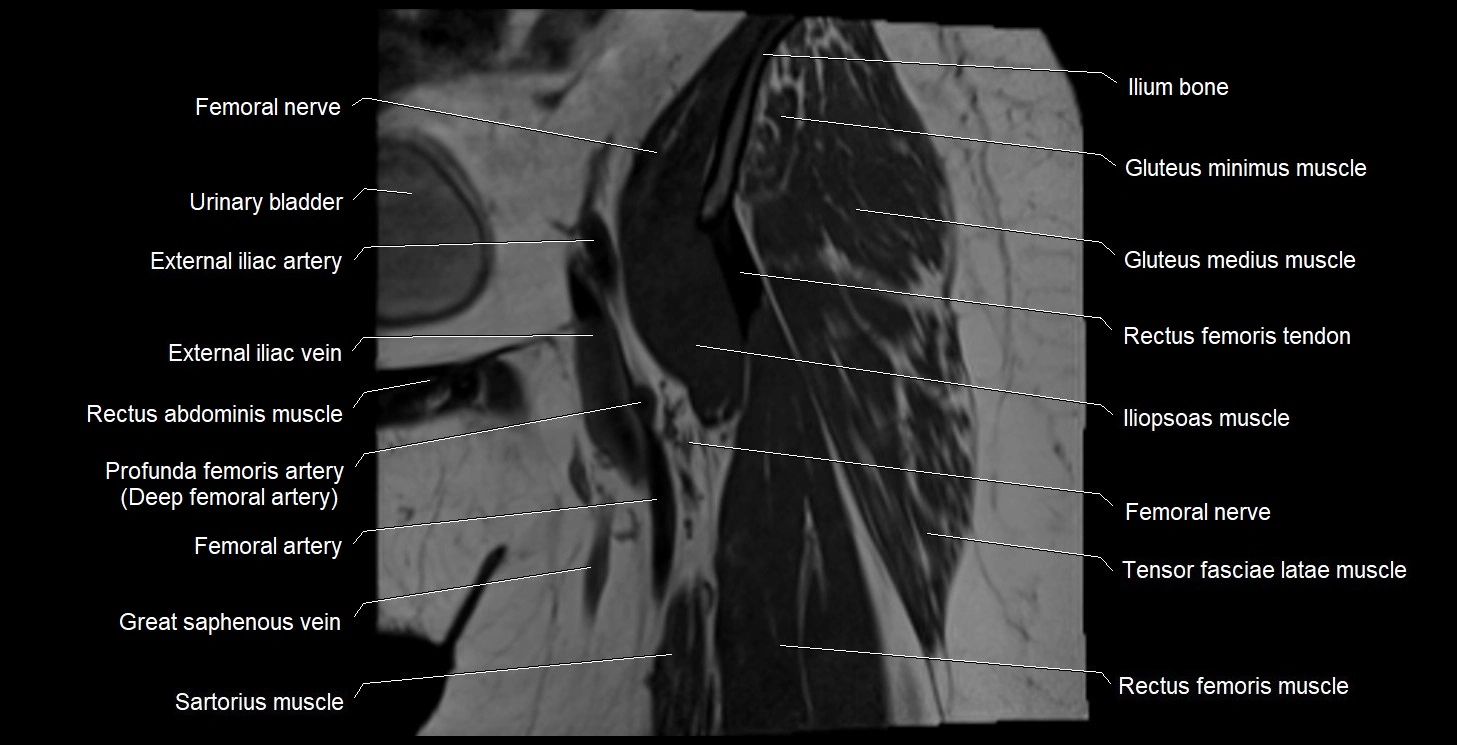

- Deep femoral artery (profunda femoris)

- External iliac artery

- External iliac vein

- Femoral nerve

- Femoral vein

- Gluteus medius muscle

- Gluteus minimus muscle

- Iliopsoas muscle

- Ilium bone

- Psoas major muscle

- Rectus femoris muscle

- Rectus femoris tendon (Proximal tendon of rectus femoris)

- Sartorius muscle

- Tensor fasciae latae muscle

- great saphenous vein